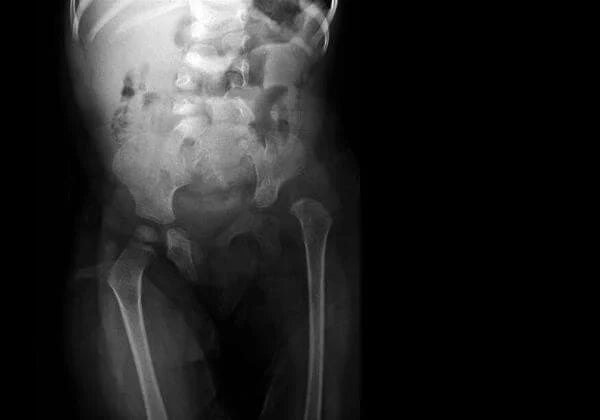

Our bones support us and allow us to move. They cushion our brain, heart, stomach, and other vital organs from injury. Our bones act as storage for vital minerals which is why it's critical to keep them healthy as you age.